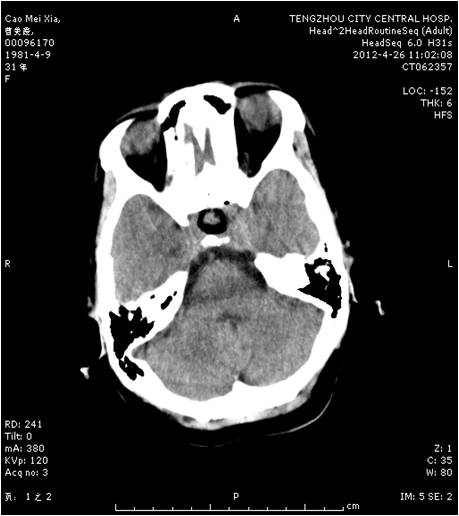

垂體瘤術前 垂體瘤術后